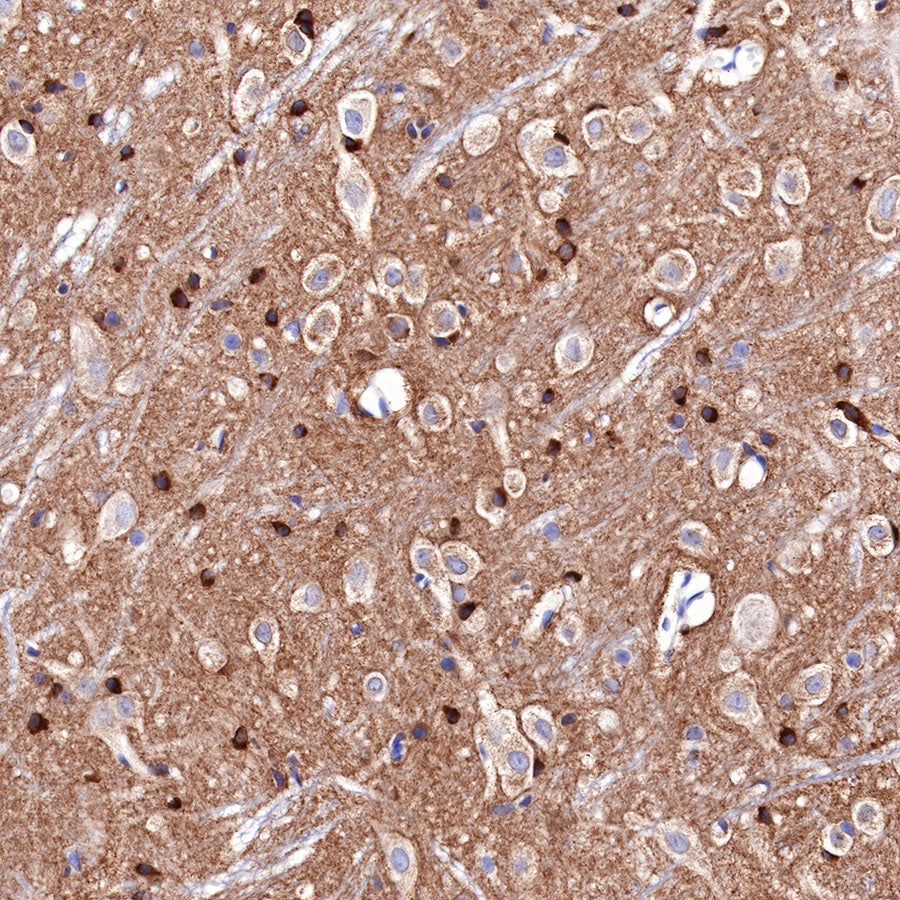

Immunohistochemistry

IHC shows positive staining in paraffin-embedded mouse cerebral cortex. Anti-Tau antibody was used at 1/2000 dilution, followed by a HRP Polymer for Mouse & Rabbit IgG (ready to use). Counterstained with hematoxylin. Heat mediated antigen retrieval with Tris/EDTA buffer pH9.0 was performed before commencing with IHC staining protocol.

IHC shows positive staining in paraffin-embedded rat cerebral cortex. Anti-Tau antibody was used at 1/2000 dilution, followed by a HRP Polymer for Mouse & Rabbit IgG (ready to use). Counterstained with hematoxylin. Heat mediated antigen retrieval with Tris/EDTA buffer pH9.0 was performed before commencing with IHC staining protocol.